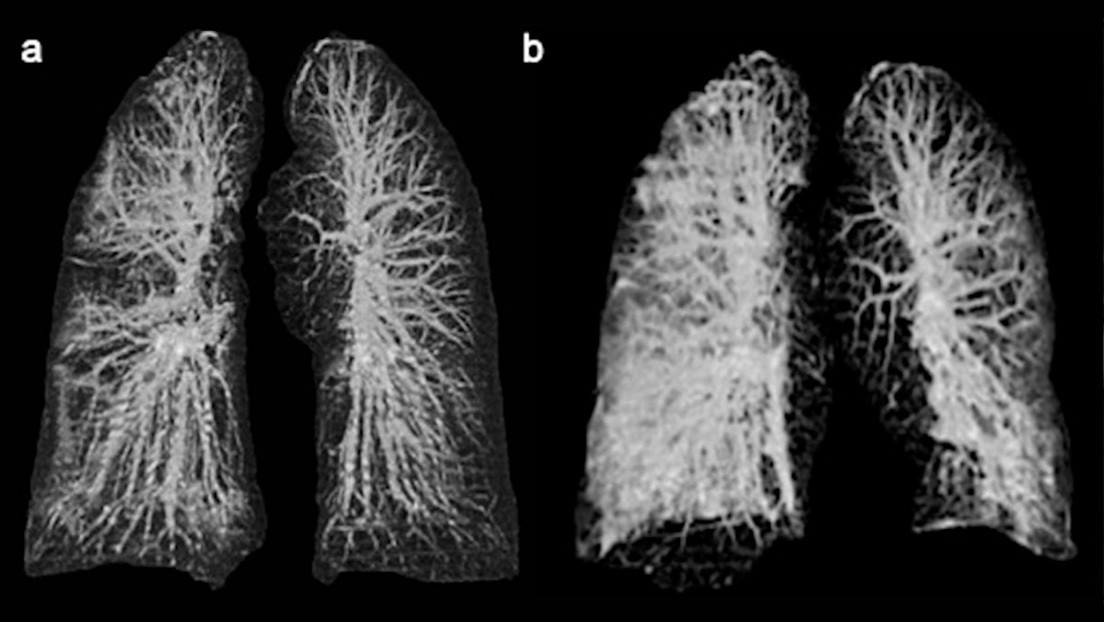

Здоровый образ жизни: Влияние курения